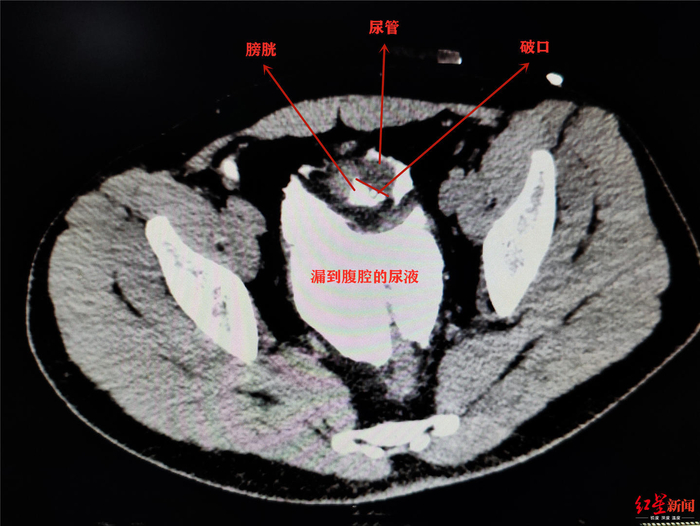

在病床上的小李说起这两天的经历,也是有些哭笑不得。上周六晚上,和朋友相约聚会吃冷啖杯、喝啤酒,期间没上过一次厕所。聚会结束后,站起身的小李脚下一滑摔了一跤,刚好肚子撞在了桌角上。这一撞,让他感觉疼痛难耐,随即被送到了就近的医院。医生先是给他安装了尿管紧急处置,经过进一步检查发现其腹腔内已经有尿液,说明是膀胱发生了破裂。

辗转几家医院,小李在星期天晚上被送到了成都市第三人民医院。该院泌尿外科副主任医师袁仁斌博士说,小李膀胱有一个4*3cm的破洞,尿管也顺着洞“跑”到了腹腔内。因为尿液在腹腔内蓄积了很长时间,已经引发了比较严重的腹膜感染,“如果再不及时手术,可能生命都会受到威胁。”